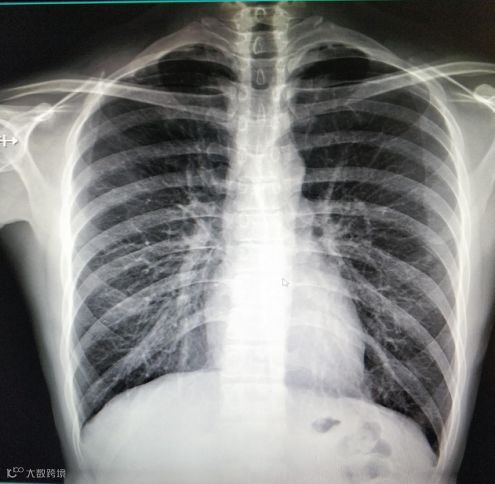

胸部——粗看X光片,细看CT

对肺、胸膜下、近横膈区和纵膈旁的病变推荐使用胸部CT检查,CT特别是对于早期肺癌确诊有决定性意义。它能清晰显示组织器官,对X线不易显示的区域,如肺、胸膜下、近横膈区和纵膈旁的病变能显示清楚,准确性均优于常规X光胸片。

X光胸片常见于筛查有无肺纹理增多、肺部钙化等病状。